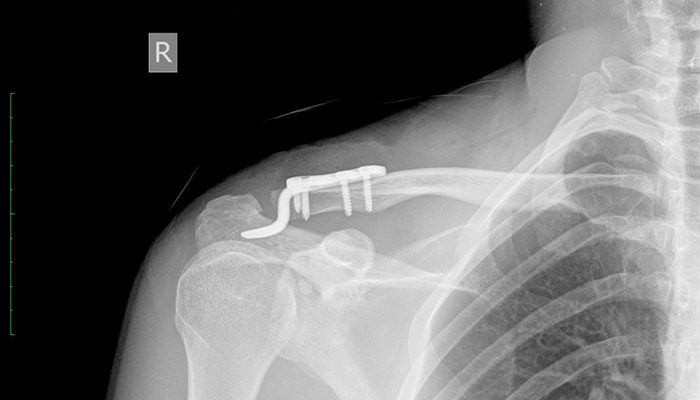

Распознать вывих достаточно просто на основании ярко выраженных внешних симптомов и собеседования с пациентом. Рентгенологическое обследование проводилось для уточнения диагноза и выявления повреждений кровеносных сосудов, нервных окончаний и близлежащих тканей.Если у врача возникают дополнительные вопросы и сомнения по поводу диагноза, рекомендуется компьютерная томография. Этот тест позволяет послойно осмотреть поврежденный участок.

Только после внимательного изучения изображений врач ставит окончательный диагноз и назначает соответствующее лечение.

Если консервативное лечение неэффективно и травма носит хронический характер, пациента направляют в больницу и оперируют вывихнутый конец ключицы. Во время него разорванные связки сшиваются, а части поврежденного сустава иммобилизуются различными способами.

Хирургическая операция

Наиболее распространены следующие оперативные методы лечения.

1. Крепление саморезами. Этот метод более надежен, но снижает подвижность конечностей в период его использования. Рецидивы случаются гораздо реже.